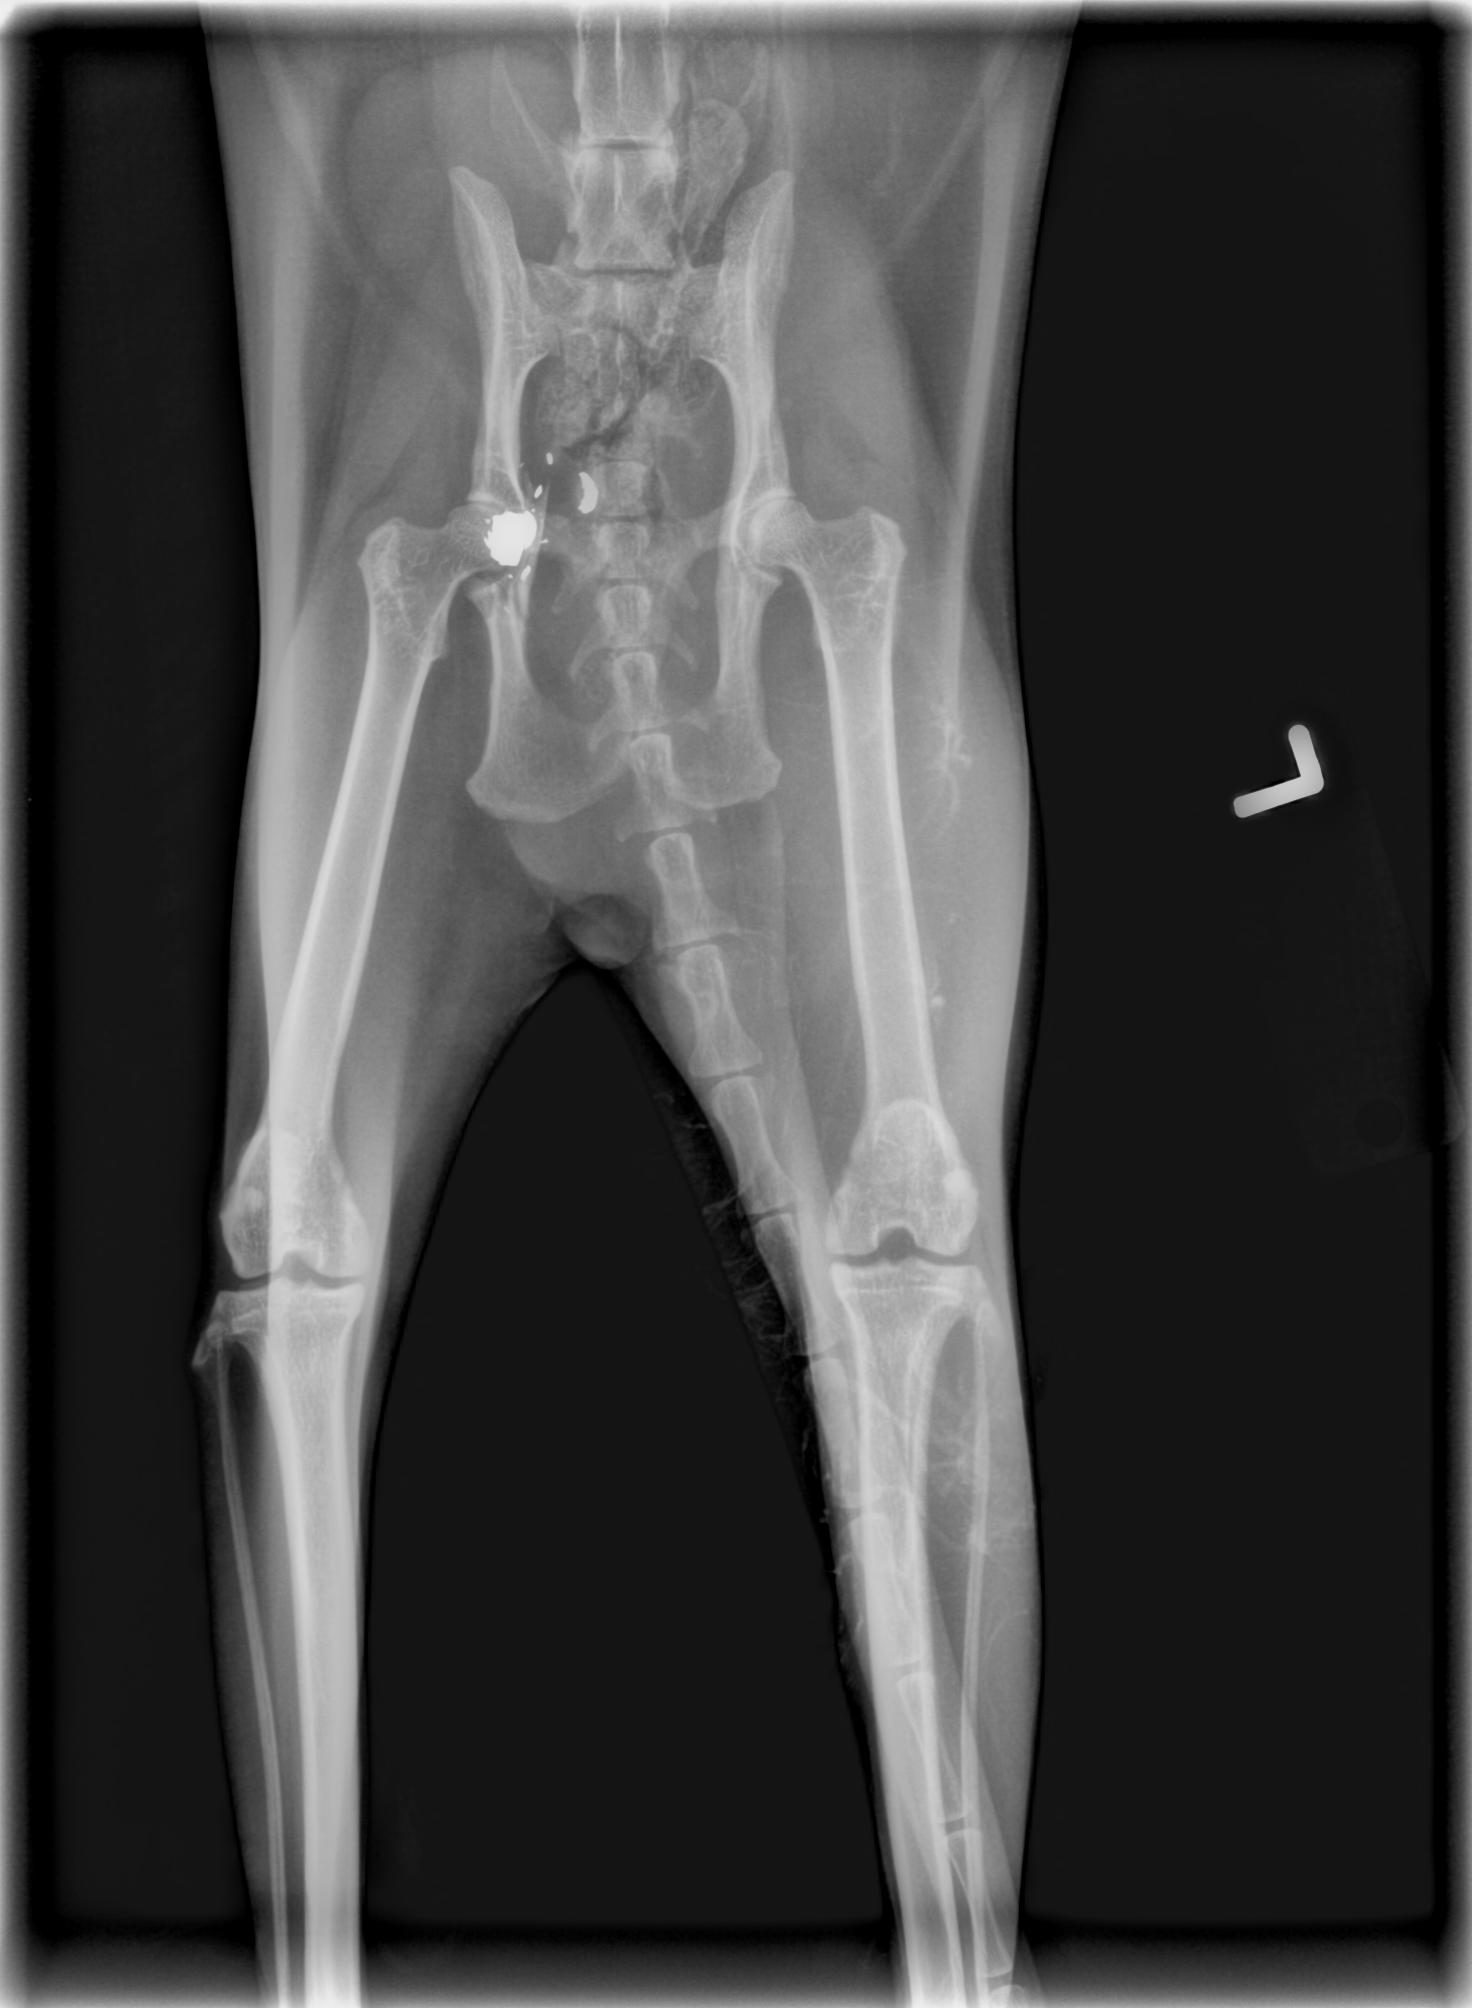

Pelvis cracked by impact of round, and you can see where some of it is way too close to the spinal column to go digging around.